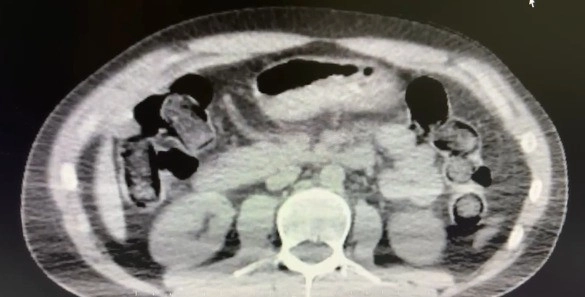

Nevşehir İl Emniyet Müdürlüğü Narkotik Suçlarla Mücadele Şube Müdürlüğü ekipleri, kentte uyuşturucu ve uyarıcı madde ticareti yapmak ve kullanmak suretiyle vatandaşları zehirleyen sokak satıcılarına yönelik çalışma başlattı. Cumhuriyet Başsavcılığı koordinesinde çalışmalarını yoğunlaştıran ekipler, şüpheliler S.B. ve O.R.’nin ’yutma yöntemi’ ile kente uyuşturucu madde sevk edeceği bilgisi üzerine operasyon düzenledi. Şüphelilerin ikametlerinde ve araçlarında yapılan aramada 101 kapsül halinde 722 gram uyuşturucu madde, 1 adet hassas terazi, uyuşturucu madde sevkiyatında yutma yönteminde kullanılan muhtelif materyaller, uyuşturucu madde ticaretinden elde edilen 20 bin 210 TL, bin 320 euro ve 10 ABD doları ele geçirildi. Emniyetteki işlemlerinin ardından adliyeye sevk edilen 2 şüpheli, çıkarıldıkları mahkemece tutuklanarak cezaevine gönderildi.